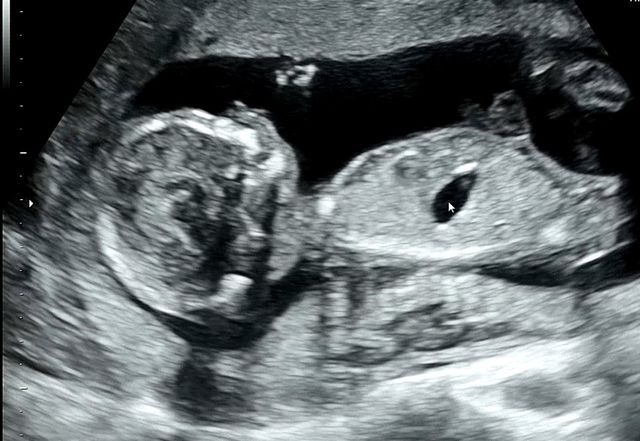

그리고 시간이 지나, 다시 찾아와 준 아이가 이제 17주가 되었습니다!

조마조마했는데 여기까지 잘 와줘서 너무 고맙고, 형님들께 자랑하려고 용기 내서 씁니다.

아 그리고, 딸입니다.. (통금 16시 확정..ㅎㅎ)